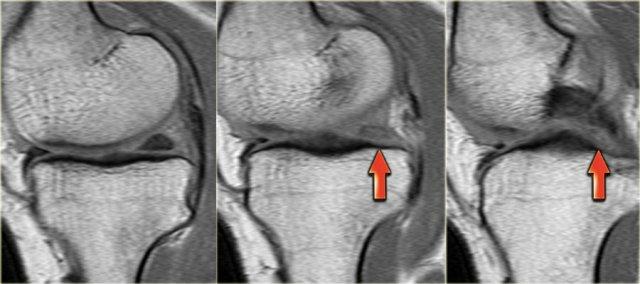

Bên trái là các hình ảnh PD sagittal của một trường hợp sụn chêm lật.

Toàn bộ sừng sau bị lật ra phía trước, tạo ra dấu hiệu sụn chêm rỗng (empty meniscus sign) (mũi tên).

Chúng ta bắt đầu với lát cắt ở giữa của khảo sát.

Lưu ý thân sụn chêm bên có kích thước nhỏ với hình dạng bất thường (mũi tên xanh).

Phần bờ trong bị khuyết được nhìn thấy ngay phía ngoài dây chằng chéo trước (mũi tên đỏ). - Phần sụn chêm bị rách di lệch vào trong, tức là phần quai xách, có thể được theo dõi theo hướng ra sau trong hố gian lồi cầu.

- Tiếp tục.

- Đây là điểm nối giữa phần quai xách và sừng sau.

- Đây là lát cắt phía trước cho thấy một nang sụn chêm.

- Lưu ý tín hiệu cao theo chiều ngang.

- Tại đây chúng ta có thể nhận thấy sự phức tạp của tổn thương rách sụn chêm với thành phần theo chiều dọc và chiều ngang (các mũi tên).

Rách kiểu quai xách là loại rách dọc theo chiều đứng có kèm di lệch.

Mảnh bờ trong bị di lệch có hình dạng giống như quai của một chiếc xô.

Phần ngoại vi còn lại của sụn chêm, phần lớn hơn, có hình dạng giống như thân chiếc xô.

Loại rách này chiếm khoảng 10% trong tổng số các trường hợp rách sụn chêm.

Dấu hiệu PCL đôi

Dấu hiệu dây chằng chéo sau (PCL) đôi là một dải giảm tín hiệu nằm song song và ở phía trước-dưới so với PCL trên ảnh MRI mặt phẳng đứng dọc.

Đây là dấu hiệu có độ đặc hiệu cao trong chẩn đoán rách sụn chêm kiểu quai xô (3).